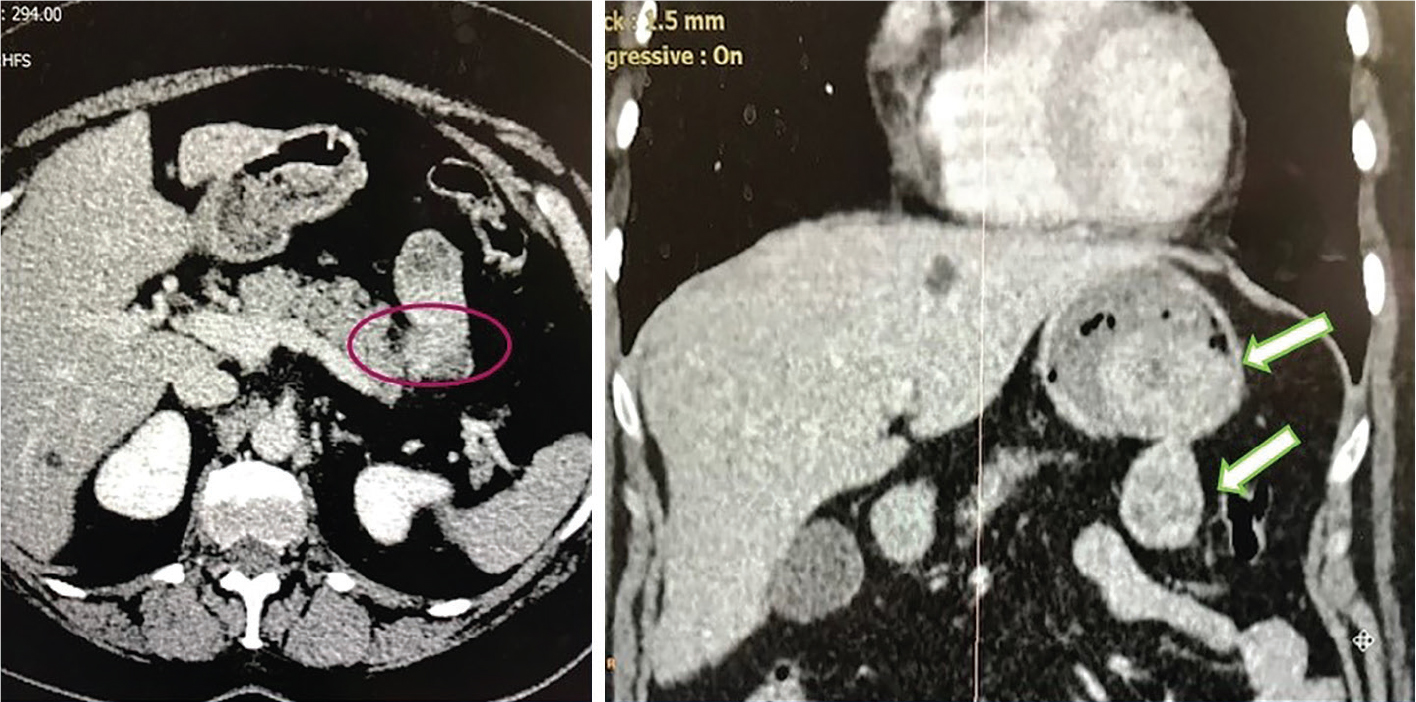

Fig 3

Figure 3. Extraluminal portion of gastric GIST. A, Laparoscopic resection. After division of the short gastric vessels on the greater curvature and along the right gastroepiploic artery, the lesser sac is opened showing a large extraluminal portion of a gastric GIST in continuity with the intraluminal portion, both located along the posterior wall of the gastric fundus and body. B, After division of the short gastric vessels on the greater curvature and along the right gastroepiploic artery, the lesser sac is opened showing multiple synchronous satellite nodules of gastric GIST located in the antrum of the same patient displayed in Figure A.